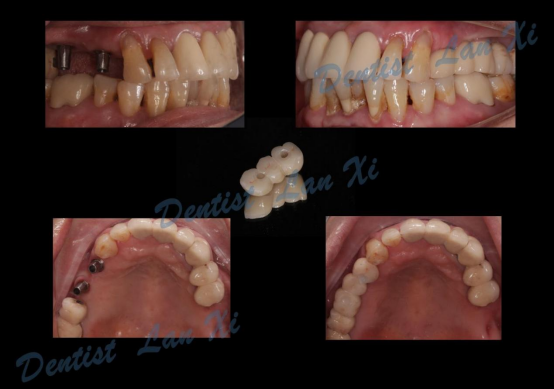

数字化种植导板引导下治疗流程

第一步:数据采集(口扫或仓扫+CBCT

第二步:数据匹配

(CBCT采集的Dicom数据与口扫获取的STL数据进行匹配,通过牙齿位点进行匹配。)

第三步:植入及导板设计

第四步:导板制作完成

(目前生成导板的方式主要有3D打印和切削两种方式)

第五步:外科手术

第六步:最终修复